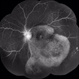

- Ocular syphilis, acute syphilitic posterior placoid chorioretinitis, OCT

- A 36-year-old male with bilateral visual loss of 3 months' duration, with no relevant medical history on inquiry. A round-shaped lesion with well-defined borders and a yellowish-white color is observed in the macula of both eyes, accompanied by vitreous cellularity. The macular OCT shows a dentate RPE. The VDRL, FTA-ABS, and HIV tests were positive.